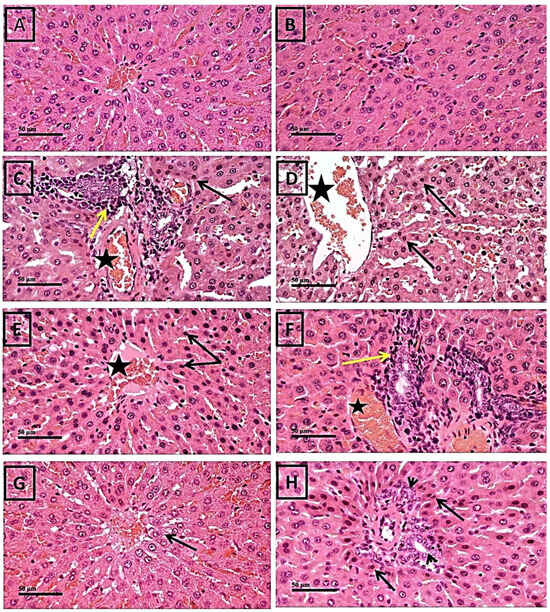

2.1. Protective Effect of Thymol against 5-FU-Induced Histopathological Changes in Liver Tissues